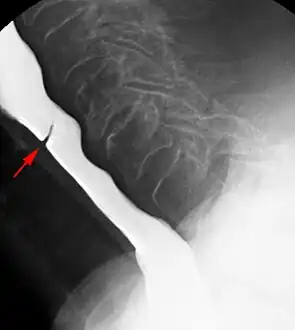

The diagnostic test of choice is a barium swallow.

Esophageal webs are thin 2–3 mm (0.08–0.12 in) membranes of normal esophageal tissue consisting of mucosa and submucosa that can partially protrude/obstruct the esophagus. They can be congenital or acquired. Congenital webs commonly appear in the middle and inferior third of the esophagus, and they are more likely to be circumferential with a central or eccentric orifice. Acquired webs are much more common than congenital webs and typically appear in the cervical area (postcricoid).